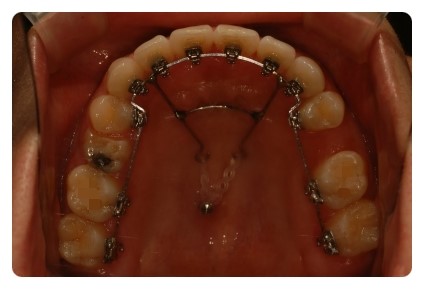

혹시 제 치아교정후기를 처음보시는 분들은 스크류가 웨 삐뚤게 되어잇나 이상하게 생각하실텐데

가운데 자리에 스크류를 심엇다가 너무 아파서 빼고 옆으로 빗겨서 다시 심엇어요

그바람에 스크류에 거는 고무줄도 한쪽은 체인3개, 다른한쪽은 4개로 당기는힘을 다르게해요

왼쪽이 몇년전에, 오른쪽이 얼마전에 발치한 자리에요

미리 발치햇엇던 치아자리 때문에 양쪽공간이 골고루 닫히지않아서 중심선이 틀어졌엇는데

위에 정면사진보시면 지금은 다시 맞아졌어요